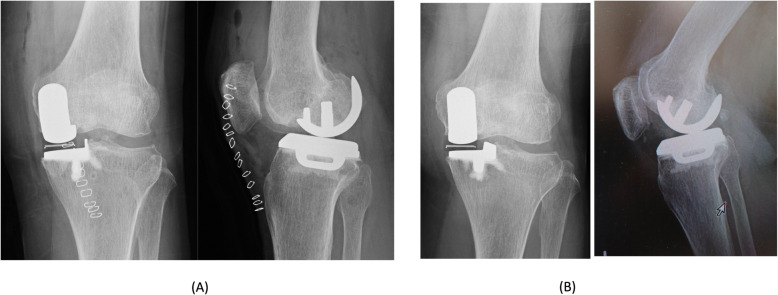

Fig. 1.

Case 1 radiographs. Postoperative plain radiographs of the left knee. a Postoperative radiographs at 1 year showing the migration of the femoral component (b)

At one-year postoperative follow-up, she felt no pain, and the Knee Society and Knee Society Functional Scores were 95 and 100 points, respectively. The ROM of the right knee was 140° flexion and 0° extension. She did not experience knee instability during her daily routine. Although radiography of the frontal plane showed migration of the femoral component, the radiographs showed no apparent loosening the femoral component, (Fig. 1b).